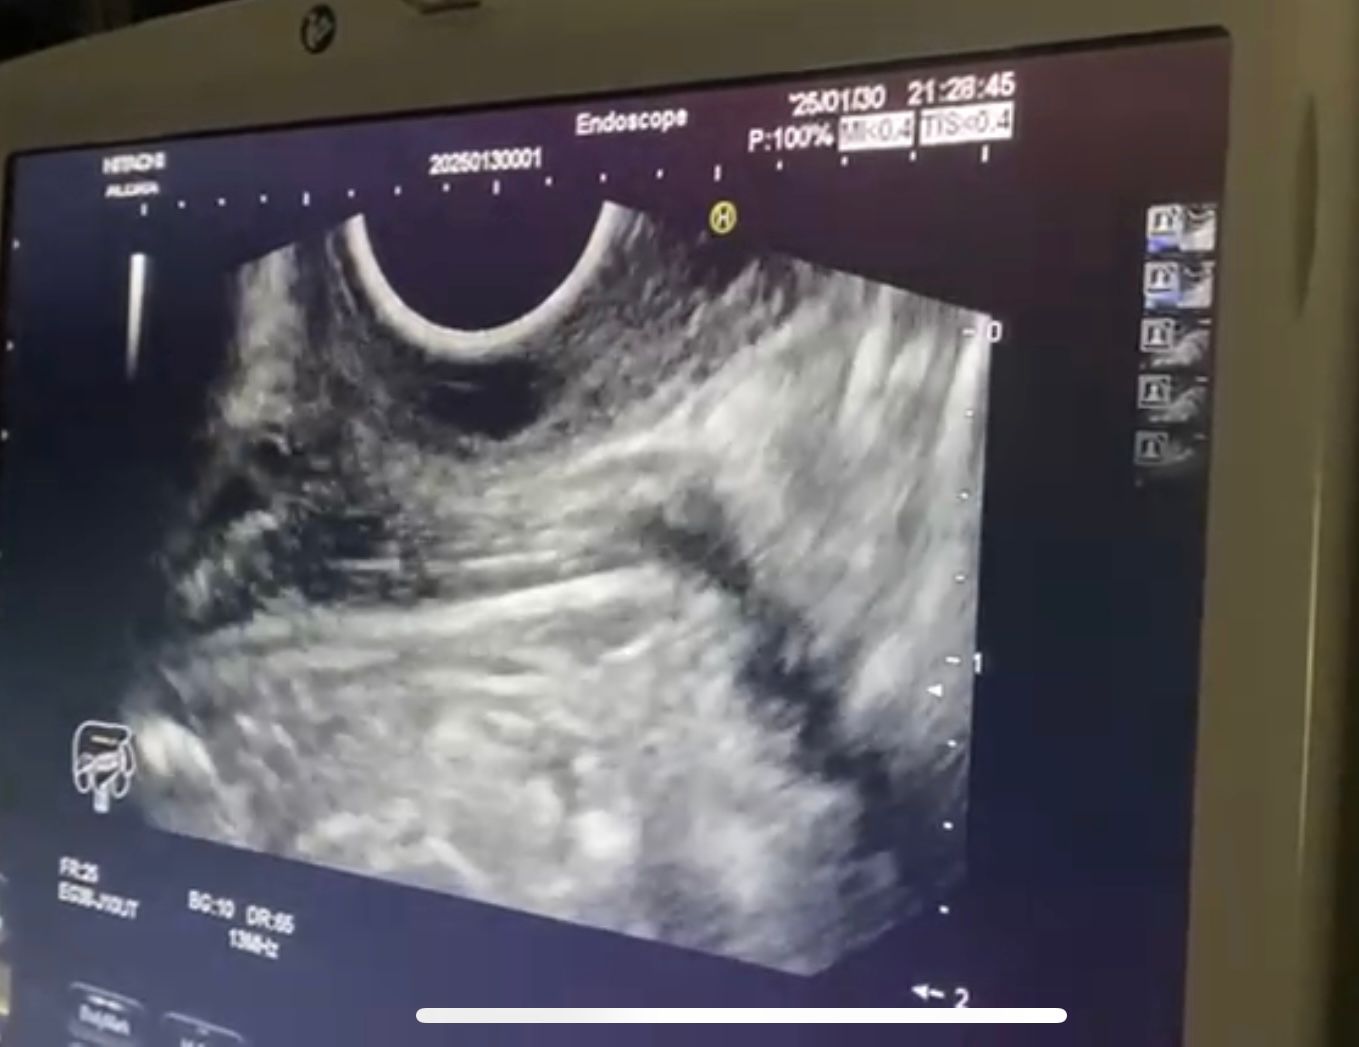

نجحت وحدة المناظير بكلية الطب في جامعة حلوان في إجراء أول عملية من نوعها باستخدام منظار الموجات فوق الصوتية لتشخيص واستئصال ورم بالمريء في نفس الجلسة. تمت العملية بمستشفى بدر الجامعي، دون الحاجة لأي تدخل جراحي، مما يمثل تطورًا كبيرًا في مجال الطب الحديث.

استغرقت العملية 30 دقيقة فقط، حيث تم استخدام تقنية مناظير الفراغ الثالث لتحديد نوع الورم، موقعه، وحجمه، ومن ثم استئصاله بنجاح في نفس الجلسة. هذا النهج الفعال ساعد في تجنب مضاعفات التخدير المتكرر، وتمكنت المريضة من مغادرة المستشفى في حالة صحية ممتازة بعد 24 ساعة فقط.

تمت العملية تحت إشراف الدكتور شريف البحيري، مدرس الباطنة العامة بكلية الطب واستشاري المناظير التداخلية، والذي تلقى تدريبًا متخصصًا في هذه التقنية المتقدمة في جامعة كاتب أتاتورك بتركيا، ضمن مهمة علمية بدعم من جامعة حلوان.